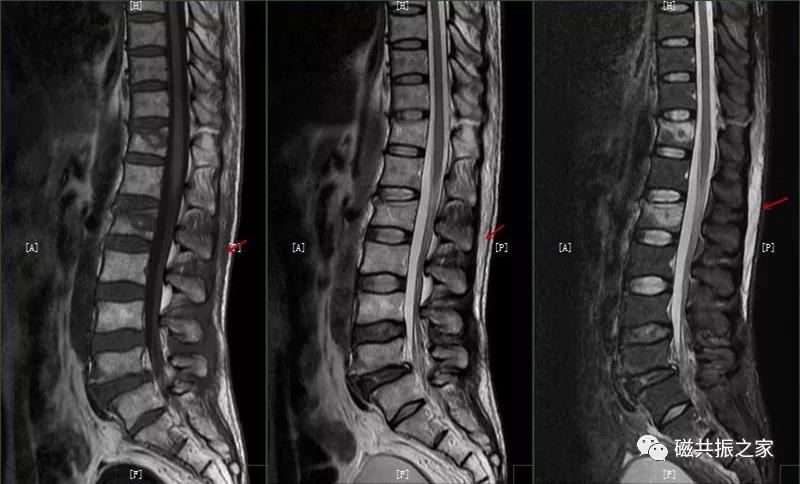

椎体边缘骨,类似于Schmorl改变,一类是椎体生长板和椎体二次骨化中心软骨发育异常,致其不能完全愈合,造成的椎间盘疝入其间,形成边缘体的椎体边缘骨。

椎体生长板和椎体二次骨化中心软骨发育异常,致其不能完全愈合,造成的椎间盘疝入其间,形成边缘体的椎体边缘骨。

另一类是椎体后缘骨内软骨结节,椎间盘疝入骨内,形成椎体后缘的Schmorl结节样改变,椎体终板及髓核等突入其中,椎体骨质增生,常见于L4、L5椎体下缘。

椎体后缘骨内软骨结节,椎间盘疝入骨内,形成椎体后缘的Schmorl结节样改变,椎体终板及髓核等突入其中,椎体骨质增生,常见于L4、L5椎体下缘。